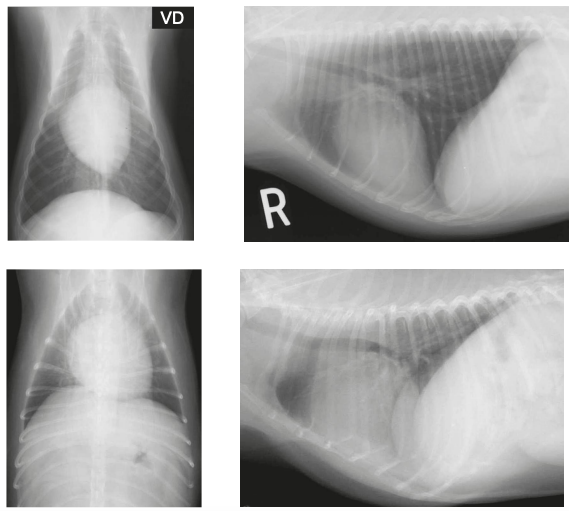

Diferencia entre ventrodorsal o supino y dorsoventral o cubitoprono. dorsoventral es mas anatomicamente correcta ya que esta mas cerca de la placa. RECORDEMOS que la ultima parte de la proyeccion es la que toca la placa (en el caso de dorsoventral, la parte ventral)

Usamos dorsoventral para ver el corazón Ventrodorsal para ver el diafragma porque es donde se inserta el diafragma y asi podemos ver los pilares del diafragma. Se ve la proyeccion de mikey mouse

Un posicionamiento incorrecto puede dar lugar a imágenes que muestren las estructuras anatómicas de forma poco familiar, lo que lleva a diagnósticos erróneos o a la dificultad en la localización de las anomalías.